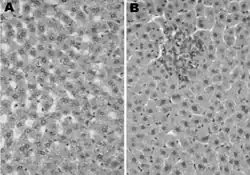

In pathology, a Councilman body, also known as a Councilman hyaline body or apoptotic body, is an eosinophilic globule of apoptotic hepatocyte cell fragments. Ultimately, the fragments are taken up by macrophages or adjacent parenchymal cells.[1] They are found in the liver of individuals suffering from acute viral hepatitis, yellow fever, and other viral syndromes.[2]

Councilman bodies were first identified in yellow fever, which characteristically shows a midzonal hepatic necrosis on biopsy. Similar inclusions are observed in other viral hemorrhagic fevers and all of the viral hepatitides. Liver biopsy of acute viral hepatitis shows panlobular lymphocytic infiltrates with ballooning hepatocytes.[4]

With a bright field microscope, Councilman described typical, discrete, necrotic lesions in human hepatic cells of those infected with yellow fever.[9] He noted that the bodies appeared to be red in hematoxylin and eosin-stained sections of hepatic tissue, while being circumscribed, varying in size, round or irregular shape, and having numerous vacuoles of different sizes.